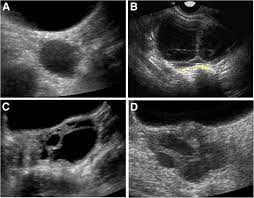

Ovarian Masses With Papillary Projections Diagnosed And Removed During Pregnancy Ultrasound Features And Histological Diagnosis Mascilini 2017 Ultrasound In Obstetrics Amp Gynecology Wiley Online Library

Ovarian Masses With Papillary Projections Diagnosed And Removed During Pregnancy Ultrasound Features And Histological Diagnosis Mascilini 2017 Ultrasound In Obstetrics Amp Gynecology Wiley Online Library from obgyn.onlinelibrary.wiley.com

When symptoms do occur, they can easily be mistaken for other conditions. These two survivors reveal how pushing for a diagnosis can. Baby brain, or forgetfulness during pregnancy happens to a lot of mothers, and it usually goes away after the pregnancy. Ovarian cancer occurs when the cells in the ovaries multiply in an uncontrolled way so that a cancerous mass is formed, called ovarian cancer. So basically i don't think that ovarian cancer could be mistaken for polycystic ovaries at this moment but on the other hand patients diagnosed with polycystic ovary syndrome are at risk of getting diabetes, hypertension and increased levels of triglyceride and cholesterol which could cause cardiovascular diseases. Well, yes, never having children seems to be associated with an increased risk of ovarian cancer, but i don't recommend getting pregnant just to decrease the risk! After pleading with one doctor to finally listen to her, she got a much more. Learn about ovarian cancer symptoms, diagnosis, treatment, and more here.

Ovarian cancer is one of the most misdiagnosed diseases because its symptoms are so similar to many benign conditions.